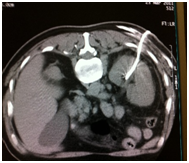

Figure 8 Nephrostomy and double J catheter insertion.

In more advanced cases cystectomy is the only choice with ileal diversion with few cases we use temporary imaging guided nephrostomy (about 10 cases) or imaging guided antegrade double J catheter insertion (I did about 4 cases ) but mostly if no serious tumor obstruction of the ureters retrograde endoscopic double J catheter insertion is effective. If the case is too advanced (terminal) we do palliative treatment to ease patient's syndromes.